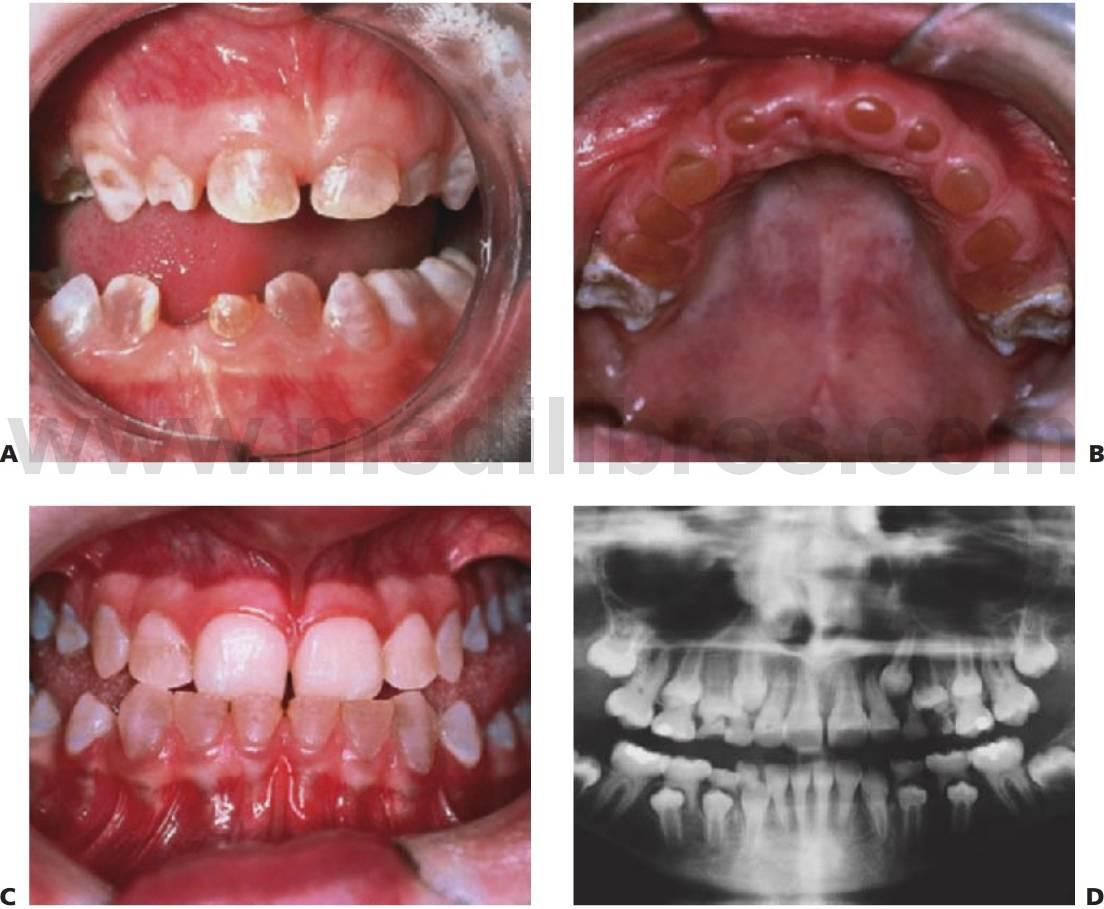

Los dientes supernumerarios surgen como resultado de una geminación de la lámina dental que se produce de forma esporádica o se heredan, como sucede con la displasia cleidocraneal (fig. 9.8).

La forma de los dientes puede recordar a la forma de las piezas normales (diente suplementario), es decir, incisiforme, caniniforme o molariforme; de no ser así, sería cónico o tuberculado.

Habitualmente se presenta como consecuencia del fallo en la erupción de uno o más dientes permanentes y en general presenta formas cónicas o tuberculadas.

Diagnóstico

- Erupción fallida o ectópica de un diente permanente (fig. 9.8B).

- Estudio radiológico rutinario.

- Como parte de un síndrome, como la displasia cleidocraneal (fig. 9.9).

- A menudo erupcionan dientes cónicos que se pueden extraer con mucha facilidad (fig. 9.8A).

- Los dientes tuberculados o cónicos invertidos requieren extracción quirúrgica (fig. 9.8D) tan pronto como sea posible para permitir la erupción sin obstáculos del diente permanente.

- Resulta esencial localizar la posición del diente que debe extraerse antes de la cirugía. Pueden realizarse radiografías periapicales que emplean la técnica del desplazamiento del tubo (tube-shift) para localizar el diente, pero siempre entrañan la posibilidad de errores e interpretaciones erróneas. De la misma manera, pueden utilizarse radiografías panorámicas y oclusales maxilares estándar. La proyección oclusal de vértice permite obtener una muestra más precisa de la localización horizontal y anteroposterior, por lo que es la preferida (fig. 9.8C) para ayudar a determinar el procedimiento quirúrgico óptimo. Algunos centros prefieren no utilizar esta vía debido a una excesiva radiación en el cráneo.

Displasia cleidocraneal (OMIM 119600)

Este trastorno se hereda con un rasgo autosómico dominante y se caracteriza por una frecuencia elevada de mutaciones espontáneas. Se ha localizado en 6p21 con mutaciones en el gen CBFA1 (fig. 9.9).

Manifestaciones

- Múltiples dientes supernumerarios (fig. 9.9A).

- Retraso en la erupción de los dientes.

- Formación de quistes dentígeros.

Debe observarse que la extracción de la dentición temporal sin exposición quirúrgica de los dientes permanentes no permite la erupción de estos últimos, por lo que se requiere una intervención en dos tiempos. En la primera operación se exponen los segmentos anteriores y se extraen los segmentos anteriores temporales y todos los dientes supernumerarios que pueda haber. Se exponen quirúrgicamente los dientes permanentes, ya sea mediante colgajos reposicionados apicalmente o mediante cadenas de oro cementadas para la tracción ortodóncica.

A continuación, los dientes anteriores se alinean ortodóncicamente. En la segunda operación se extraen los molares temporales, se extraen quirúrgicamente los dientes supernumerarios restantes y se exponen los premolares y molares en los segmentos bucales. Posteriormente se procede al tratamiento ortodóncico definitivo y puede requerirse la realización de una cirugía ortognática en los casos de maloclusión de clase III esquelética grave. Resulta evidente que el tratamiento es muy prolongado en el tiempo y el odontólogo debe valorar los problemas potenciales relacionados con el cumplimiento del tratamiento por parte del niño.